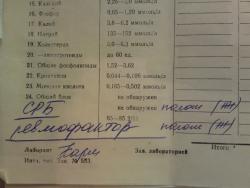

И, может быть, окажется важным